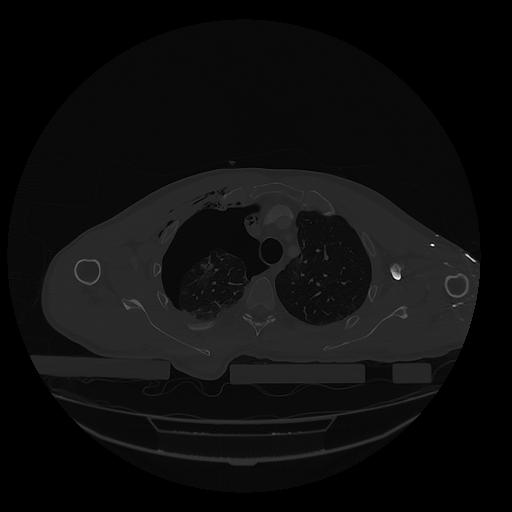

31 PULMON,CE,Vol,1.0,PULMON,,